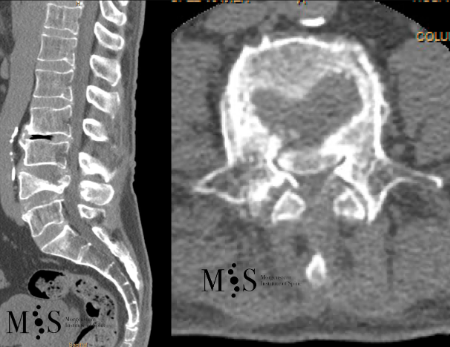

Caso clínico con estabilización percutánea de fractura vertebral inestable.

Estabilización percutánea de fracturas vertebrales inestables

En casos de fracturas vertebrales complejas, inestables, conminutas, etc. se requiere una estabilización adicional de la fractura mediante una artrodesis percutánea, y en algunos casos en los que hay compromiso neurológico, una descompresión del canal medular. La artrodesis percutánea permite estabilizar la estrctura comprometida de la columna vertebral y descargar la carga del paciente sobre la fractura. Adicionalmente se suelen cementar las vertebras artrodesas y la fractura vertebral mediante cifoplastia.